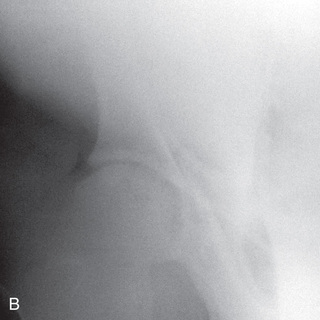

General anesthesia is required for the pelvic radiographic study of a large animal patient. Young foals (or calves) can be successfully radiographed in the field, whereas larger patients (horses or cows) must be radiographed in the hospital setting because of the specific high-powered radiographic equipment required, such as a mobile or ceiling-mounted unit, to provide proper output (high kV exposure). Views may be segmented to obtain a complete pelvic view (multiple images used for a single view). If using film, the use of a table with an embedded cassette tunnel is preferred to increase ease of positioning and cassette exchange. Due to the thickness of this region, the use of a grid is suggested.

Before administration of a general anesthetic, special consideration must be given to the anesthesia recovery process for patients with pelvic fractures or luxation. As a result, a pelvic radiographic study may be contraindicated.